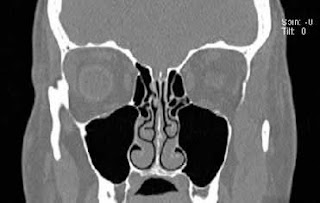

"There is an opacified mass inside the right maxillary sinus cavity [or some other sinus cavity] two centimeters [or larger] in size."Compare the above CT scan (red arrow pointing to the mass) with a normal CT scan of the sinuses below: